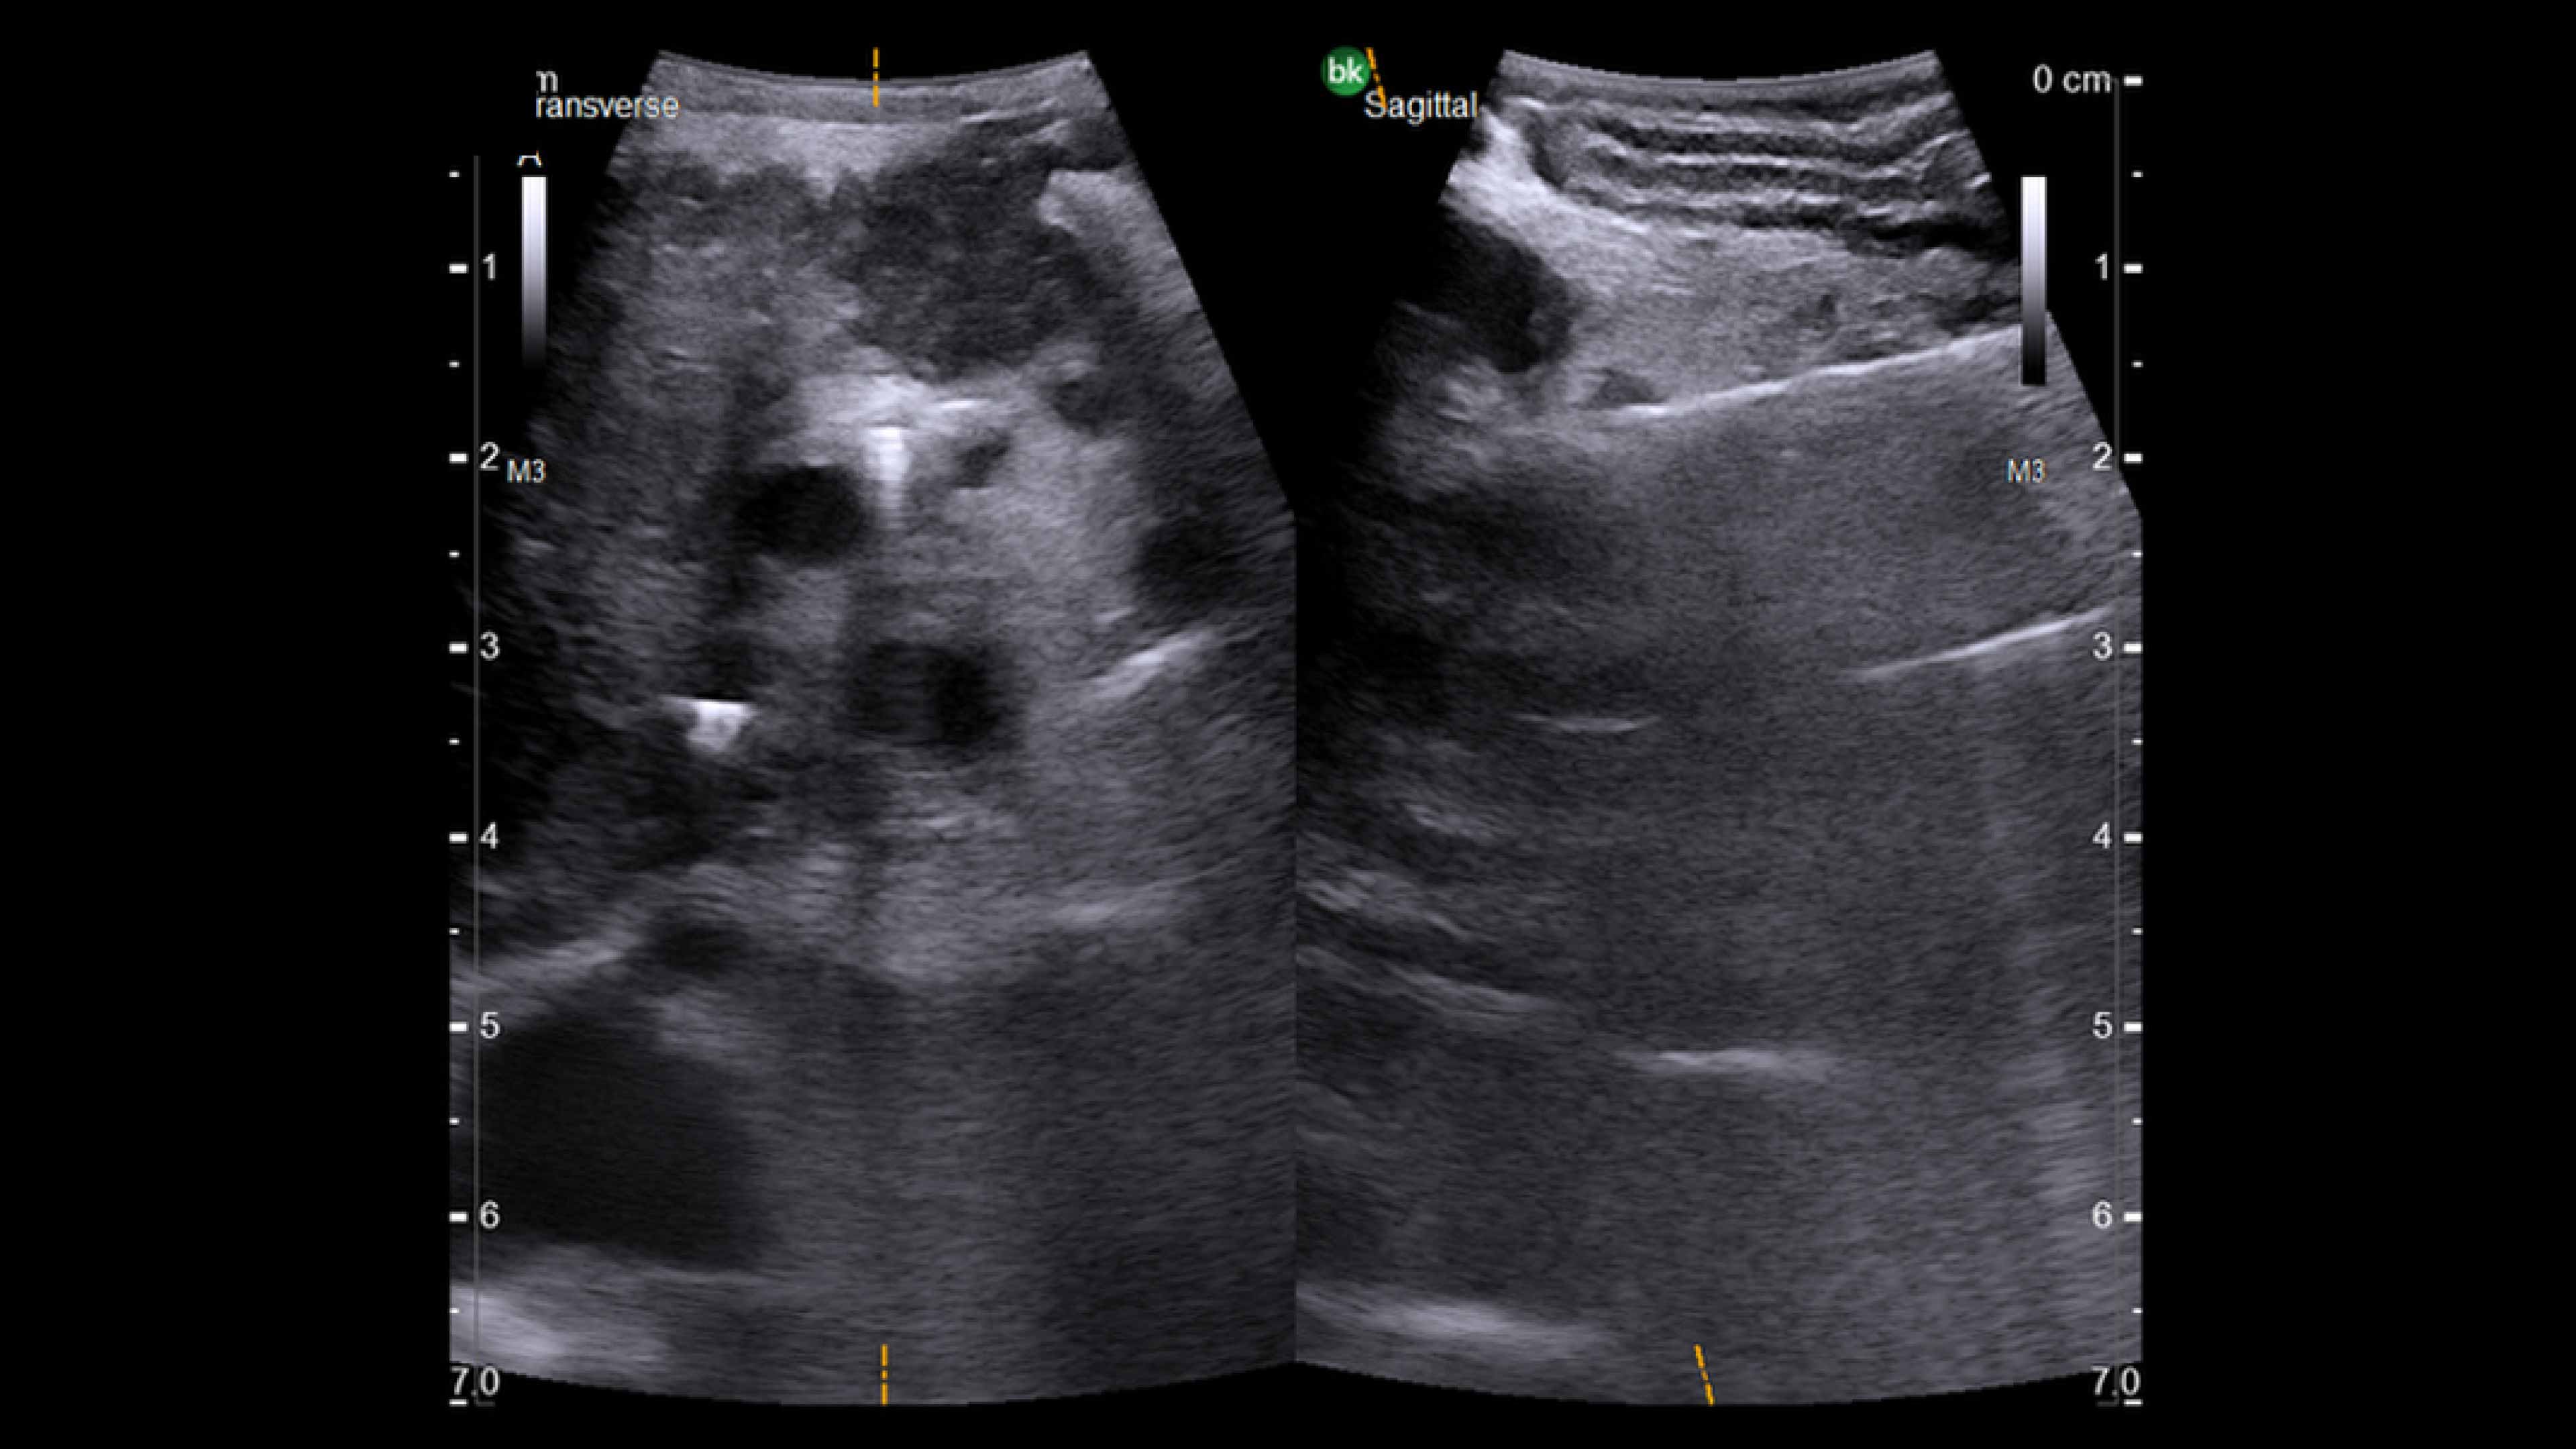

Minimally invasive surgery ultrasound

A complete portfolio of solutions for open, minimally invasive, or combined procedures. Fully sterilizable, specialized transducers designed for biopsies, tumor resections, needle placements, and ablations.

Active imaging with intraoperative ultrasound supports critical decision-making in open or minimally invasive tumor resections.

• Enable visualization of disease staging at the time of surgery with excellent image quality.

• Visualize complex anatomical variations and identify tumor location.

• Define adequate margins of resection.

• Guide and view needle placements.

• Assess surgical planning and check for vessel patency at the end of the procedure.

Read case study: Use of ultrasound during two stage laparoscopic liver resection.